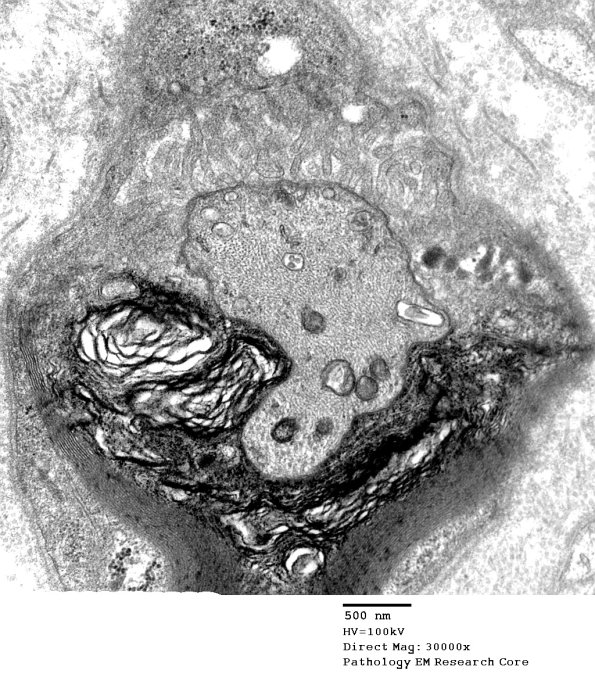

9A1,2 Many nodes may be asymmetrically cut and produce a questionable appearance of a node but the axolemma, microvilli and increase in axonal organelles is evidence for its presence (electron micrographs)